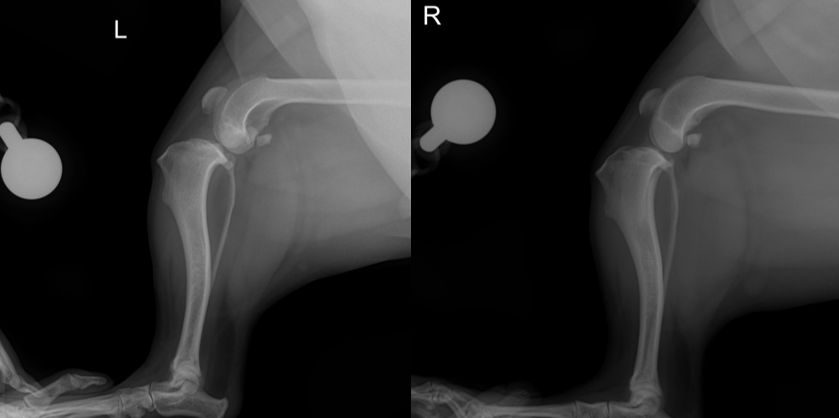

- 방사선 검사

.png)

X-ray는 십자인대 자체를 “직접” 보는 검사는 아니지만, 이미 진행된 osteoarthritis(관절염) 변화나 관절 주변 뼈 변화가 있는지 확인하고, 파행의 다른 원인이 될 수 있는 골절, 종양 같은 질환을 감별하는 데 도움이 됩니다.

또한 십자인대가 완전히 끊어진 것이 아니라 일부만 손상된 경우처럼 진단이 애매할 수 있는 상황에서는, X-ray에서 보이는 간접 소견들이 판단에 도움을 줄 수 있어 권장됩니다.

아이의 경우 좌측 stifle X-ray에서 관절염 변화와 함께 cranial cruciate ligament 파열에서 흔히 보이는 정강이뼈가 앞쪽으로 밀려난 소견이 보여 무릎의 불안정성이 의심되었습니다.”